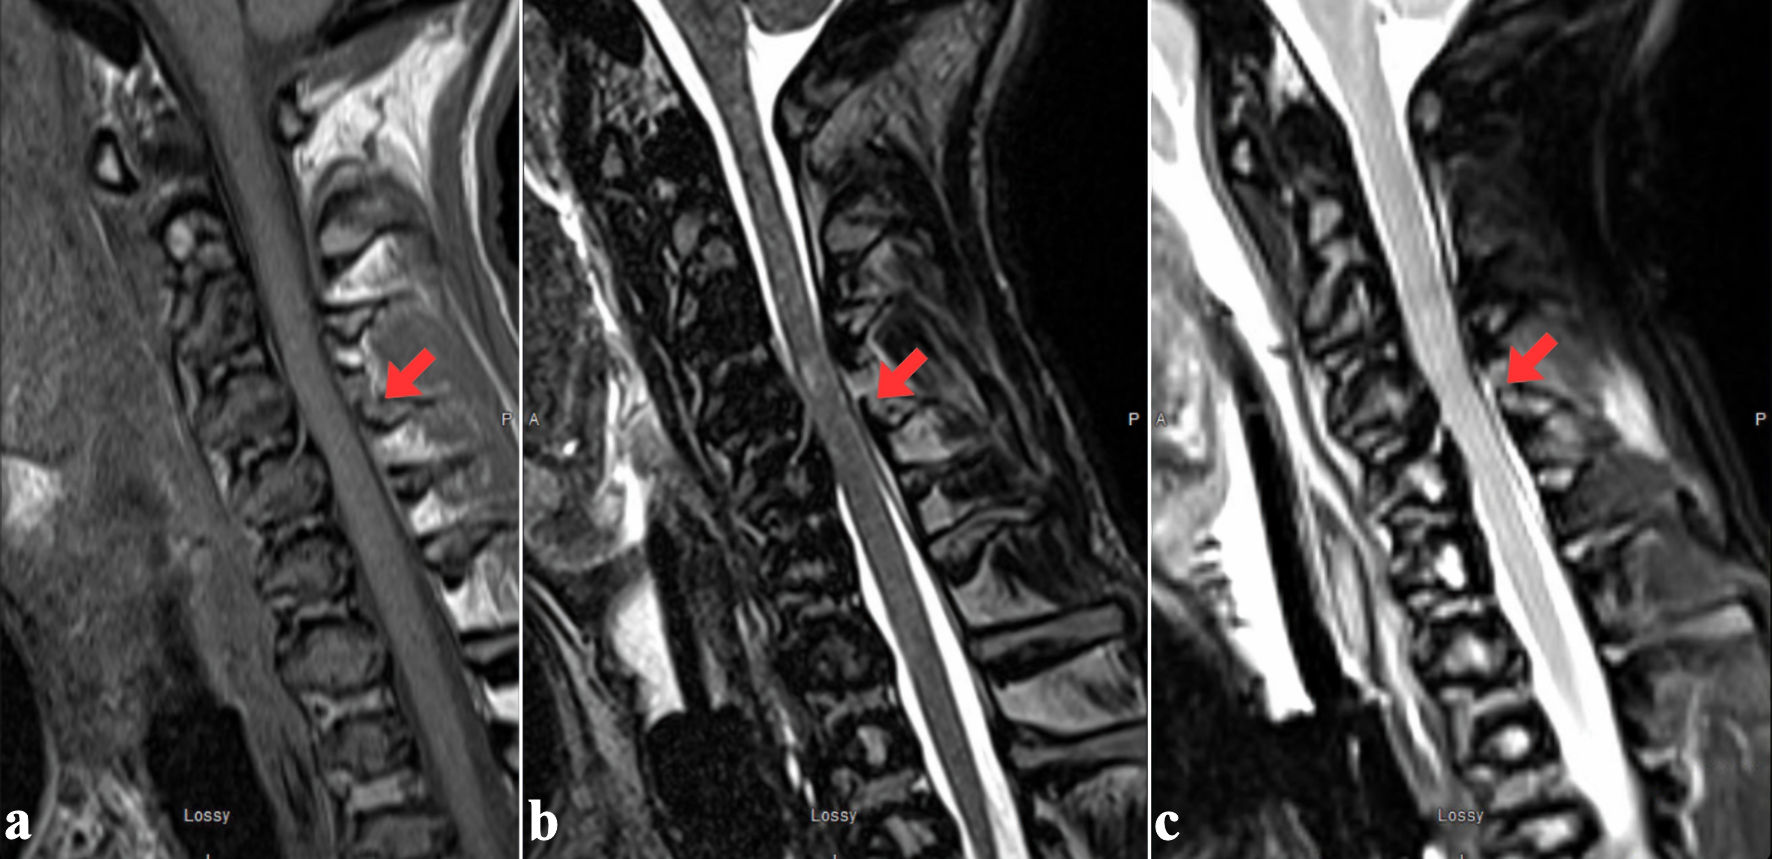

CT identified a displaced fracture of the posterior C4 vertebral body and a complex fracture of the left C4 lateral mass (involving the pedicle, lamina, transverse foramen, and both articular facets). It also showed nondisplaced fractures of the left C6 pedicle and the left C3 inferior facet (Fig. 1).

Figure 1. Axial (a) and sagittal (b) views of C4 vertebral body showing displaced fracture involving the posterior aspect of the C4 vertebral body and left lateral mass of C4, with involvement of the pedicle, lamina, transverse foramen and the superior and inferior articular facets. A nondisplaced fracture of the left inferior articular facet of C4 (red arrow) and pedicle of C6 (not shown) is also present.